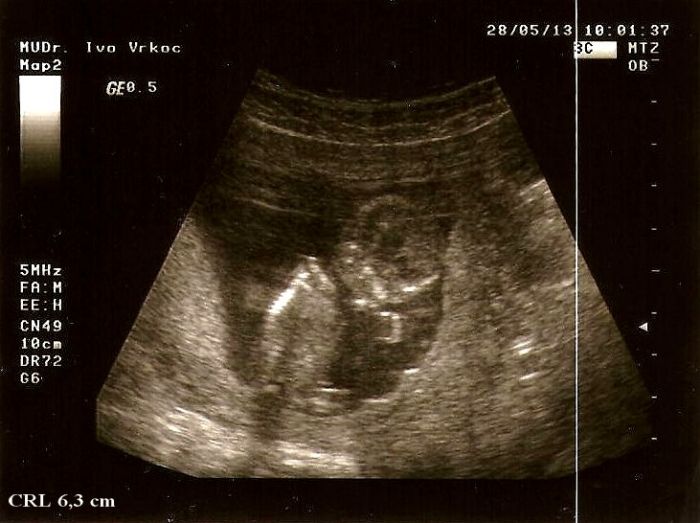

Mrňousek nám nejdřív spinkal,ale jak ho dr. probral tím šťoucháním a dloubáním,hned bylo zle a začal sebou šít o 106,rozhazoval ručičky,nožičky a hezky mamince mával(nebo se vztekal

),musela jsem se u toho smát jak to bylo úžasný

Pak nás měřil a CRL máme už 6,3 cm a odpovídáme podle jeho přístroje 12+3tt,přitom když jsem to zadala na netu do jedné tabulky spočítalo mi to už někde 12+6tt(což yb přesně odpovídalo pdole posledního utz v nemocnici) ,i když říkal,že záleží i na přístroji,že každý má ty výchozí hodnoty trochu jinak nastavený takže + - ,ale vyrostli jsme krásně..

Posílám foto broučka jak vám hezky mává ze svýho domečku